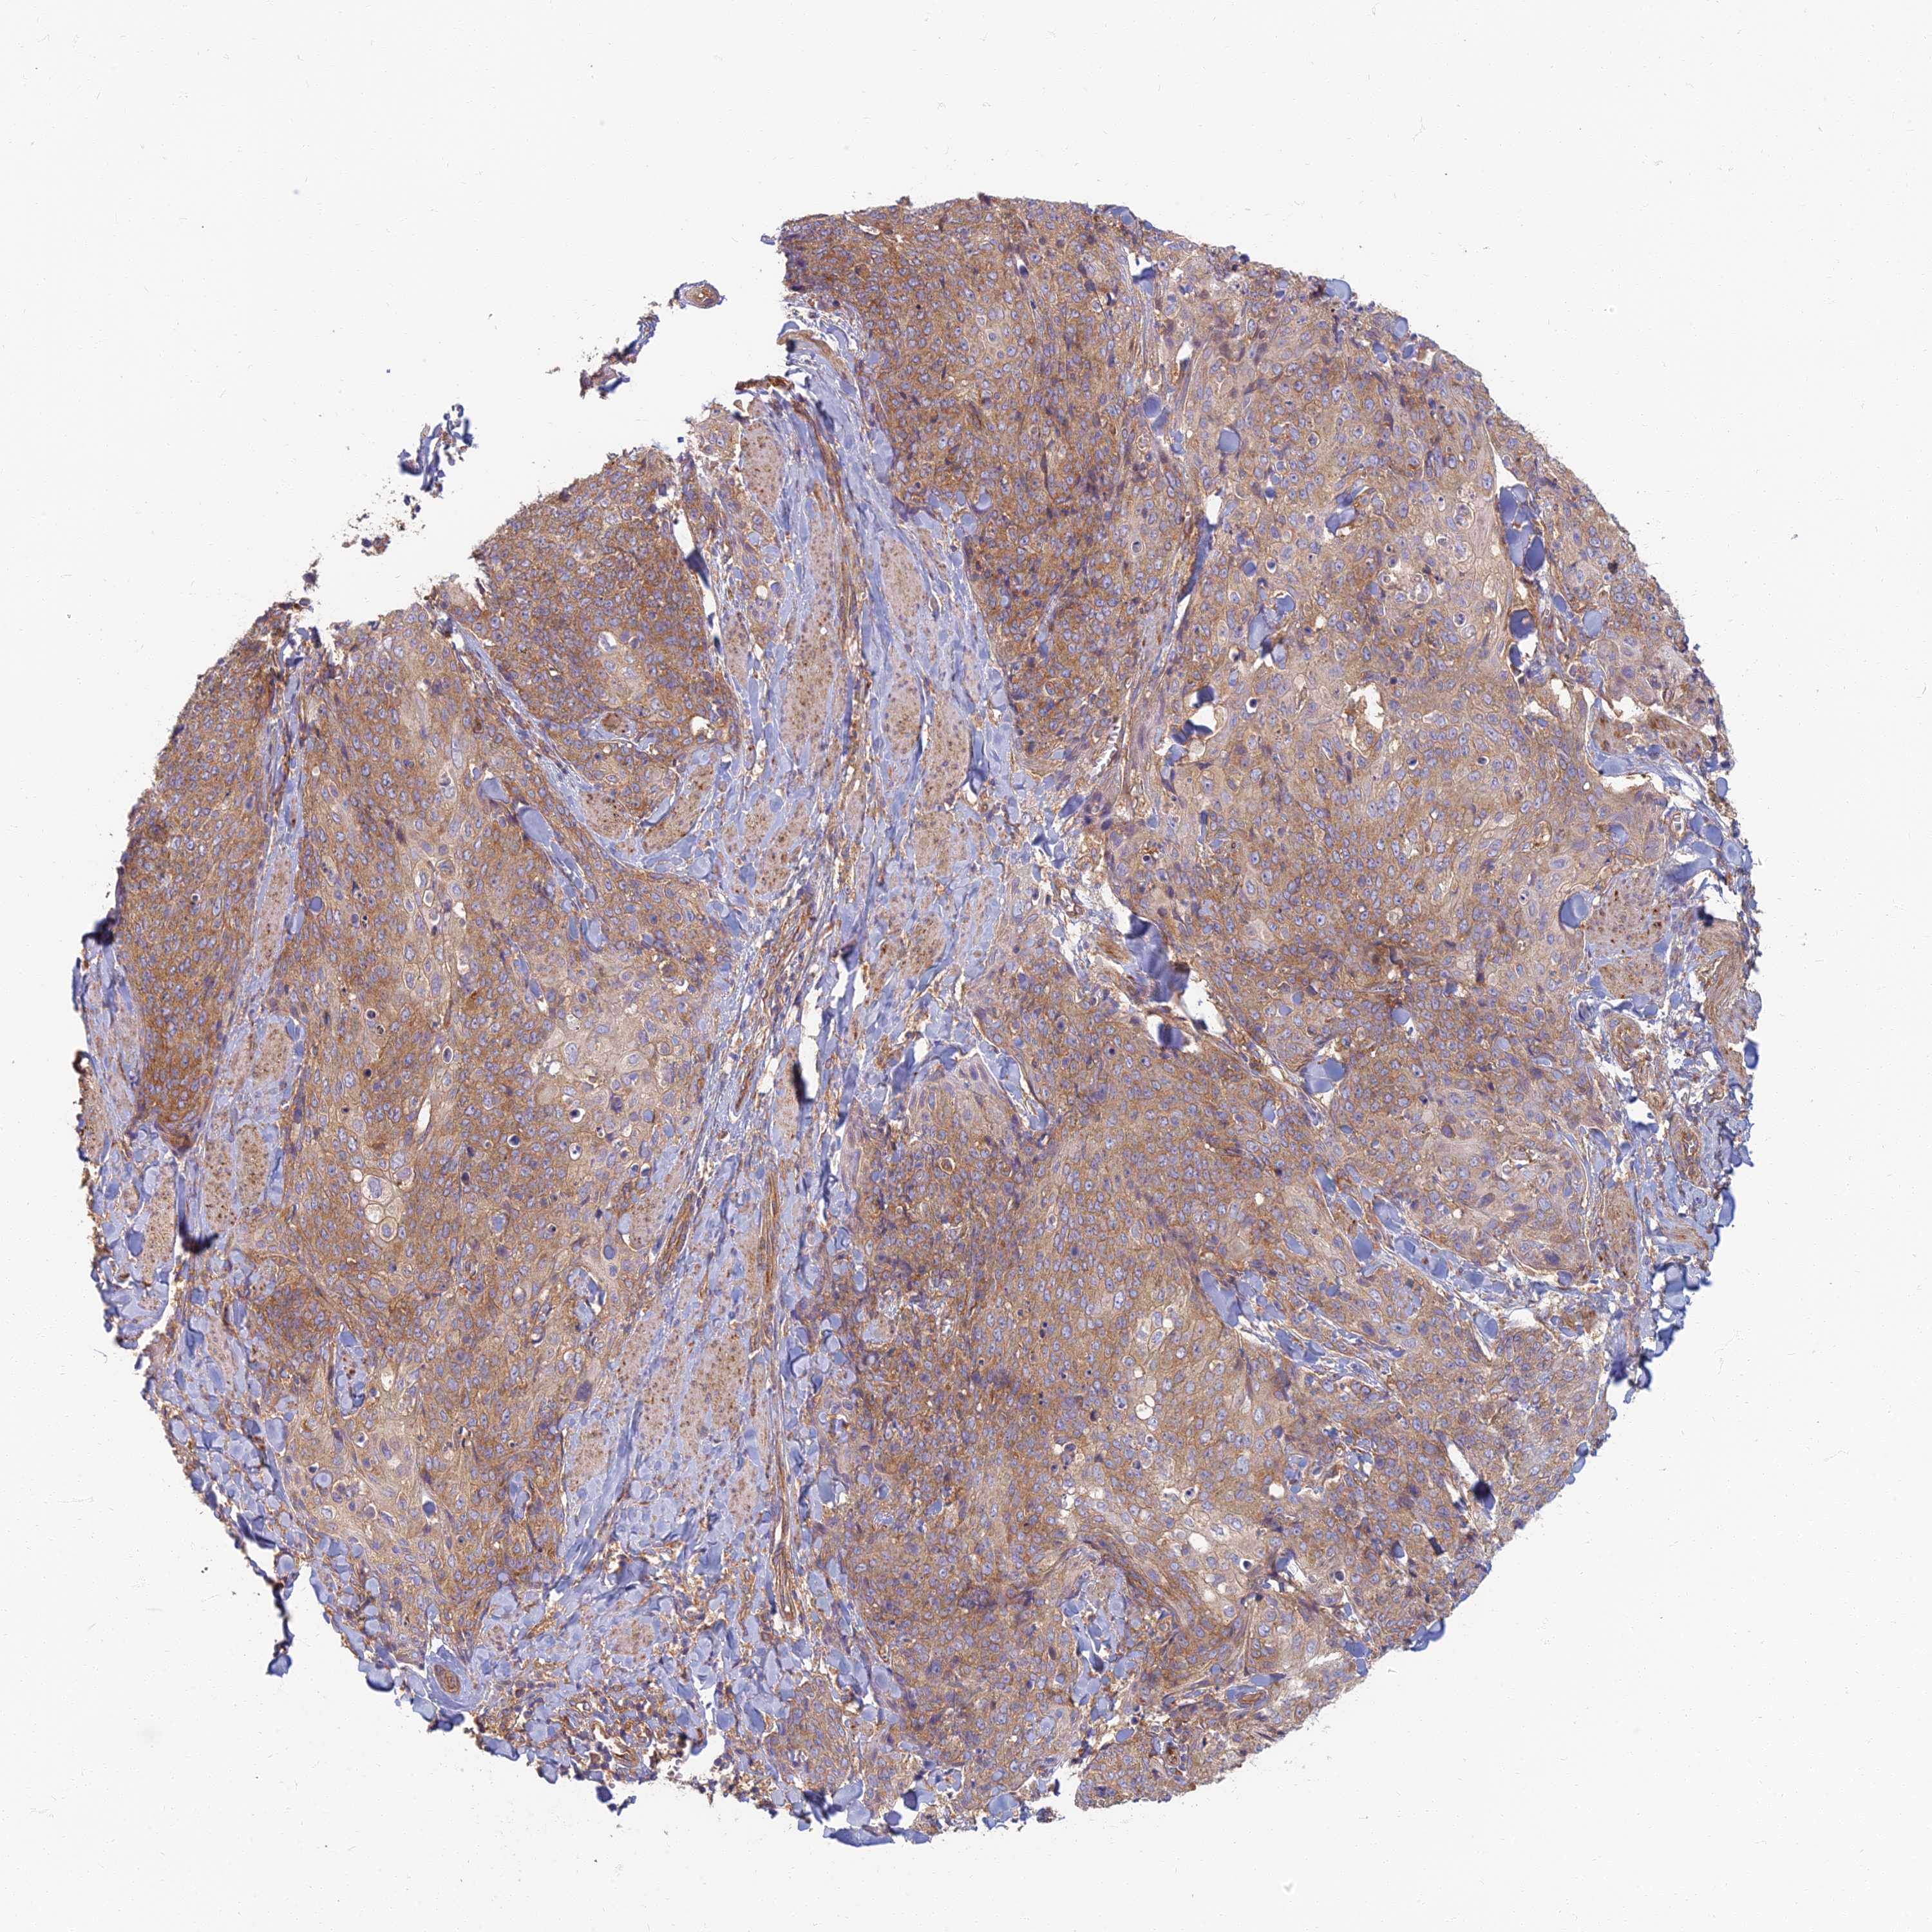

SKIN CANCER - Protein expressioni

A mouse-over function shows sample information and annotation data. Click on an image to view it in a full screen mode. Samples can be filtered based on level of antibody staining by selecting one or several of the following categories: high, medium, low and not detected. The assay and annotation is described here.

Each image is clickable and will lead to virtual microscopy that enables deeper exploration of all samples and also displays staining intensity scores, fraction scores and subcellular localization as well as patient and tissue information for each sample.

Antibody HPA044878

Staining

Medium

Intensity

Moderate

Quantity

75%-25%

Location

Cytoplasmic/membranous

Squamous cell carcinoma, NOS